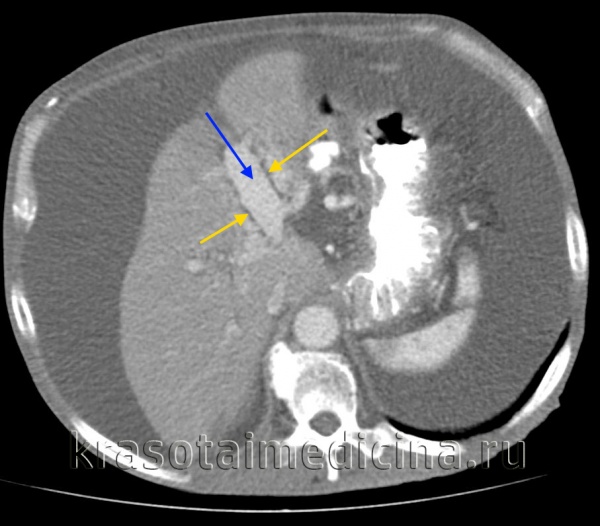

КТ ОБП. Портальная гипертензия на фоне обструкции воротной вены опухолью поджелудочной железы (красная стрелка). Опухолевый тромб (зеленая стрелка) в воротной вене. Асцит (белая стрелка).

КТ ОБП. Этот же пациент, расширенный левый долевой ствол воротной вены (синяя стрелка) с периваскулярным отеком (желтая стрелка).

КТ ОБП. Этот же пациент, варикозно расширенные вены как проявление синдрома портальной гипертензии (коричневая стрелка).